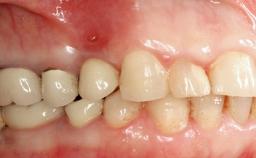

Oral implants are highly successful and offer long-term benefits, especially in the rehabilitation of edentulous patients or patients with oral defects following ablative tumor surgery (Albrektsson and coworkers 1986), and also after radiation therapy (Schiegnitz and coworkers 2014). With the number of implants placed globally going into the millions, implant dentists have observed some rare adverse events. Although carcinogenesis around implants is an exceedingly rare phenomenon, we recently reported about 15 patients treated for carcinomas adjacent to implants at our clinical department over a period of fifteen years (Moergel and coworkers 2014). The following case represents a patient of this cohort; it discusses possible risk factors and makes suggestions for a recall schedule. A 70-year-old woman was referred to our outpatient department for evaluation of a rapidly growing macroscopic alteration of the mucosa in the left mandible.